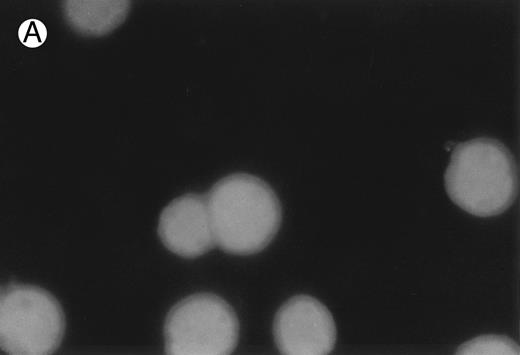

CD437-induced apoptosis in HL-60R cells. HL-60R cells were grown as described in the Materials and Methods and exposed to either vehicle alone or CD437 (1 μmol/L) for 24 hours and then stained with aciridine orange. (A) Cells exposed to only vehicle. (B) Cells exposed to CD437 (1 μmol/L).